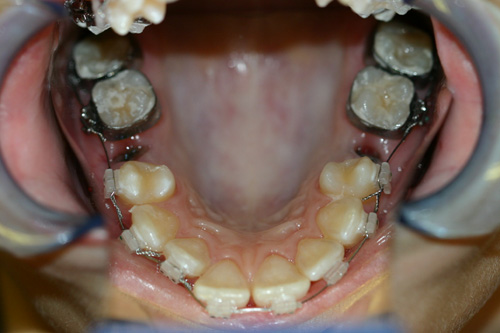

Rapid Maxillary Expansion Appliances

These appliances come in various designs. The patient is given a pen-sized wrench to do 1/4 turn per day. This rapidly widens the upper arch.

After rapid maxillary expansion.